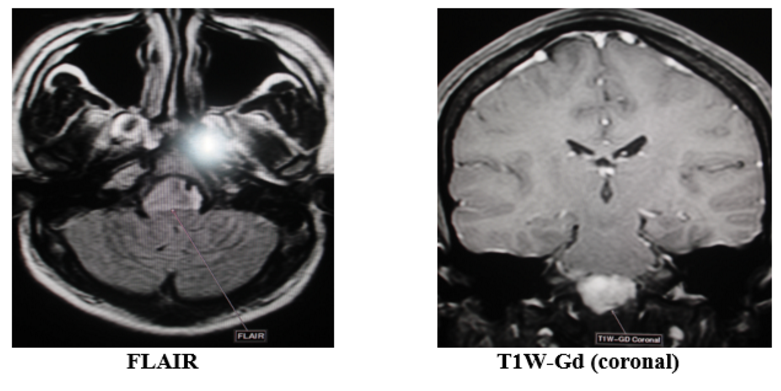

Nhân một trường hợp u màng não lờ chậm Ngày 06/08/2016, Bệnh viện quân y 121 – Cục Hậu cần Quân khu 9 đã tiếp nhận bệnh nhân Đ.C.L, sinh năm 1991, thường trú tại Long mỹ – Hậu Giang. Bệnh nhân bị bệnh nhiều năm nay, đã được chẩn đoán và điều trị bệnh viêm…